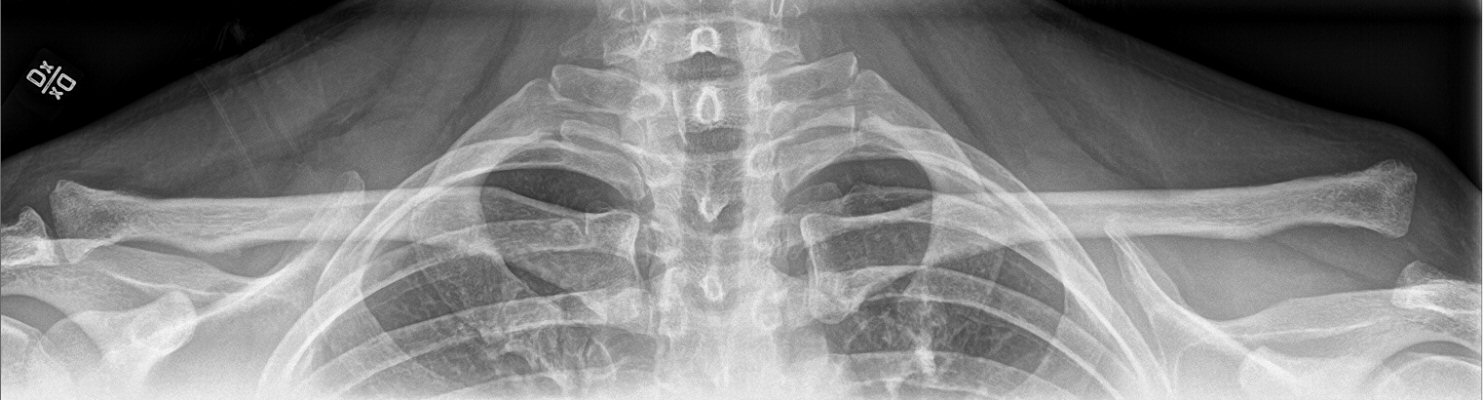

Beställ röntgen av båda AC-leder, helst med bred bild så båda finns med på samma bild, behöver ej vara belastad. Felställning kan mätas som skillnad i avstånd mellan klavikel och korakoideus på de båda sidorna.

Luxerad AC-led Rockwood III dislocerad ca 22 mm. Opererad med hook-platta som togs bort 4 månader senare